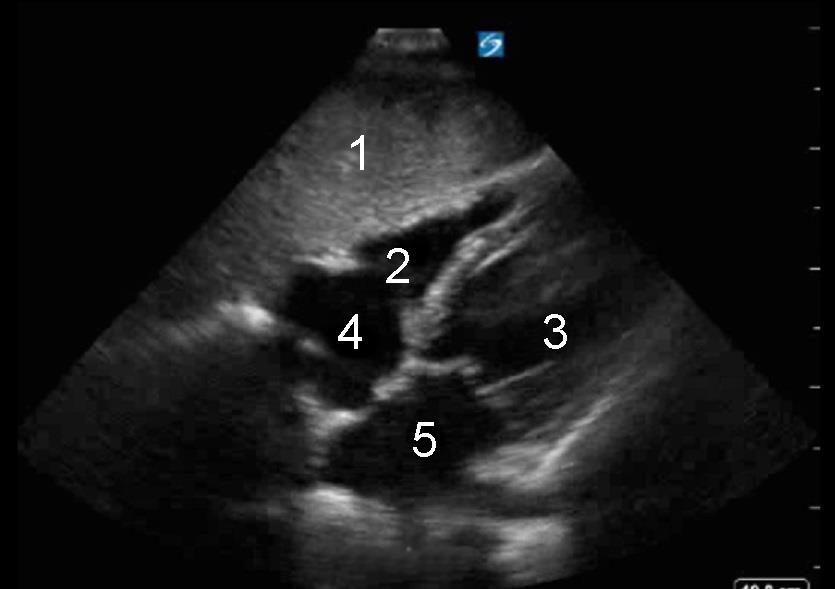

Cardíaco: Vista desde el plano subxifoideo - Imagen

1. Hígado

2. Ventrículo derecho (VD)

3. Ventrículo izquierdo (VI)

4. Aurícula derecha (AD)

5. Aurícula izquierda (AI)